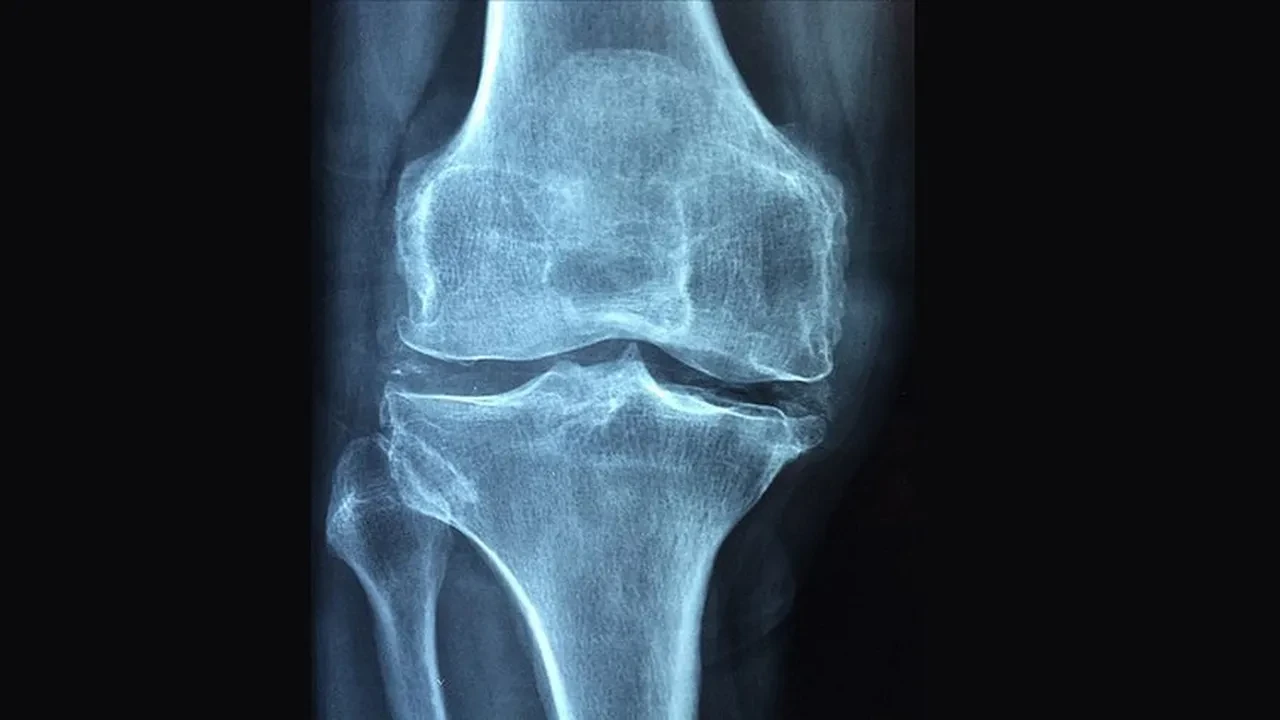

KTÜ Farabi Hastanesi Ortopedi ve Travmatoloji Bölümü’nden Doç. Dr. Muhammet Salih Ayas, kemik tümörlerinin tedavisinde erken teşhis ve doğru cerrahi planlama sayesinde günümüzde birçok hastada uzuv kaybının önlenebildiğini söyledi.

Kemik tümörü cerrahisinde önemli bir dönüşüm yaşandığını belirten Ayas, bu gelişmenin hem cerrahi tekniklerdeki ilerlemeler hem de tanı yöntemlerindeki hassasiyet artışıyla mümkün hale geldiğini ifade etti.

Kemik tümörlerinin tedavisinde "ekstremite koruyucu cerrahi" yöntemlerinin giderek daha fazla tercih edildiğini vurgulayan Doç. Dr. Ayas, "Günümüzde hedef sadece tümörü vücuttan uzaklaştırmak değil aynı zamanda hastanın hareket kabiliyetini, günlük yaşam fonksiyonlarını ve genel yaşam kalitesini en üst düzeyde korumaktır" dedi. Bu yaklaşımın, hastaların sosyal hayata daha hızlı ve sağlıklı şekilde dönmesine önemli katkı sağladığını belirtti.

Tedavi sürecinin tümörün biyolojik yapısına, yerleşimine ve yayılım durumuna göre şekillendiğini kaydeden Doç. Dr. Ayas, iyi huylu tümörlerde genellikle daha sınırlı ve koruyucu cerrahi müdahalelerin yeterli olabildiğini söyledi. Kötü huylu tümörlerde ise tümörün yalnızca görünen kısmının değil, çevresindeki potansiyel riskli dokularla birlikte çıkarılmasının hayati önem taşıdığını ifade etti. Bu yaklaşımın, hastalığın tekrar etme riskini azaltarak uzun dönem tedavi başarısını artırdığını dile getirdi.

Cerrahi tedavinin, hastalığın türü, hastalığın evresi ve hastaya özgü klinik özelliklere göre kemoterapi ve radyoterapi ile desteklenebildiğini aktaran Doç. Dr. Muhammet Salih Ayas, tanı sürecinde ileri görüntüleme teknikleri ve biyopsi uygulamalarının büyük bir titizlikle yürütüldüğünü belirtti. Doğru tanının, tedavi planlamasının en kritik aşamalarından biri olduğuna dikkat çekti.

Ameliyat sonrası oluşan kemik ve doku kayıplarının modern rekonstrüksiyon yöntemleriyle başarıyla giderilebildiğini ifade eden Ayas, "Biyolojik teknikler, hastaya özel geliştirilen protezler ve kemik transferleri sayesinde hem anatomik bütünlüğü yeniden sağlıyor hem de hastalarımızın fonksiyonlarını en iyi şekilde korumayı hedefliyoruz" diye konuştu.